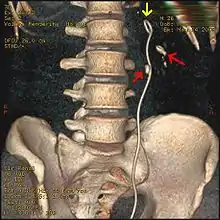

Bilateral kidney stones can be seen on this KUB radiograph. There are phleboliths in the pelvis, which can be misinterpreted as bladder stones.

Bilateral kidney stones can be seen on this KUB radiograph. There are phleboliths in the pelvis, which can be misinterpreted as bladder stones.